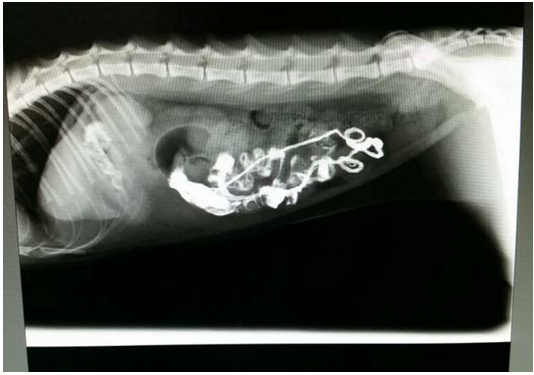

Figure 1

Lateral Radiograph after 12 hours of barium sulphate meal revealing pleated or plicated appearance of the intestinal loop suggestive of linear foreign body